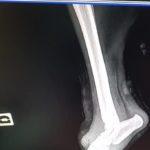

Жестоко насилие над куче край Кърджали. Животното е с отрязани задни крайници и без едно око. То е било намерено до язовир „Студен кладенец“. За щастие на помощ са му се притекли от фондация „Animal Hope Bulgaria“.

Лъки-Иван се лекува с антибиотик. Добрата новина е, че инфекцията вече е овладяна.